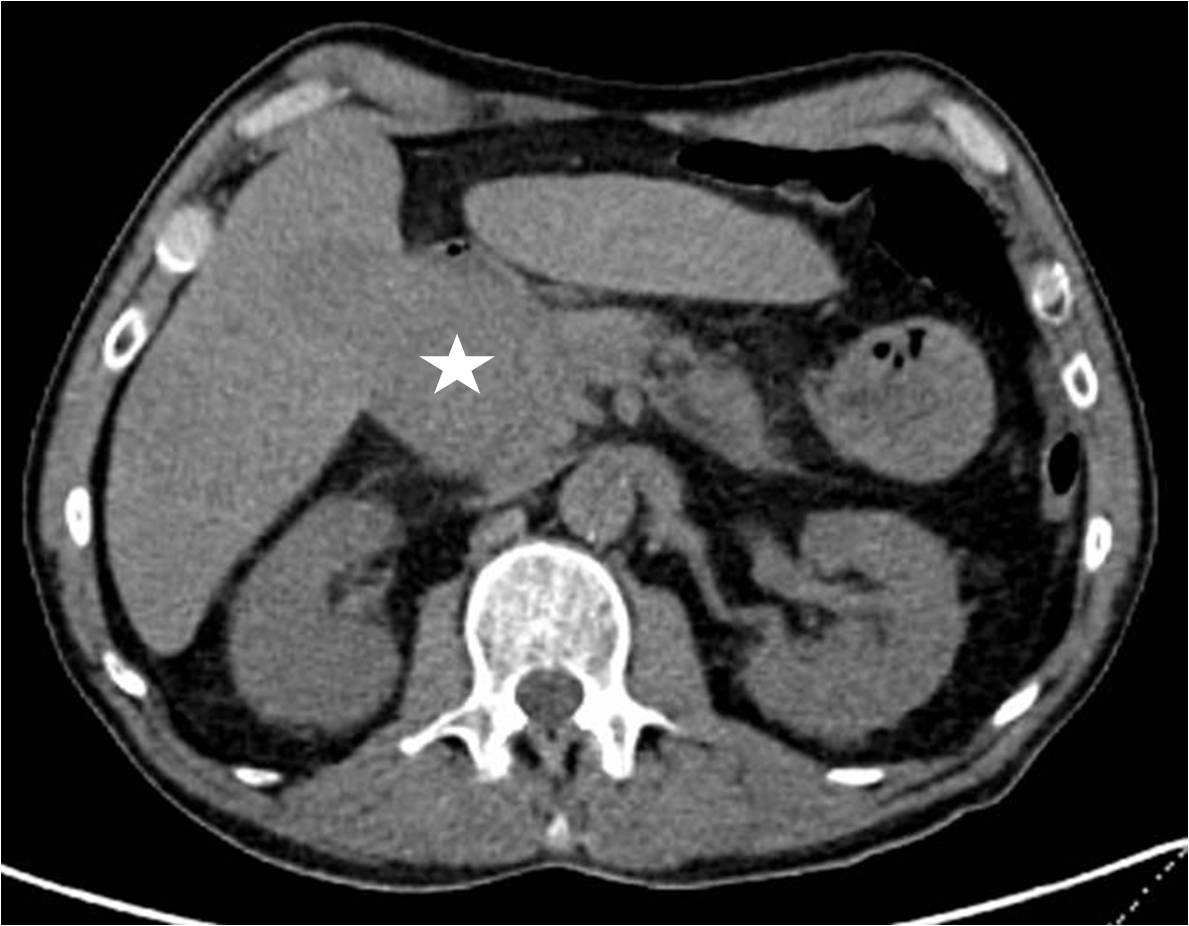

Image: Liver biopsy.

Liver biopsy